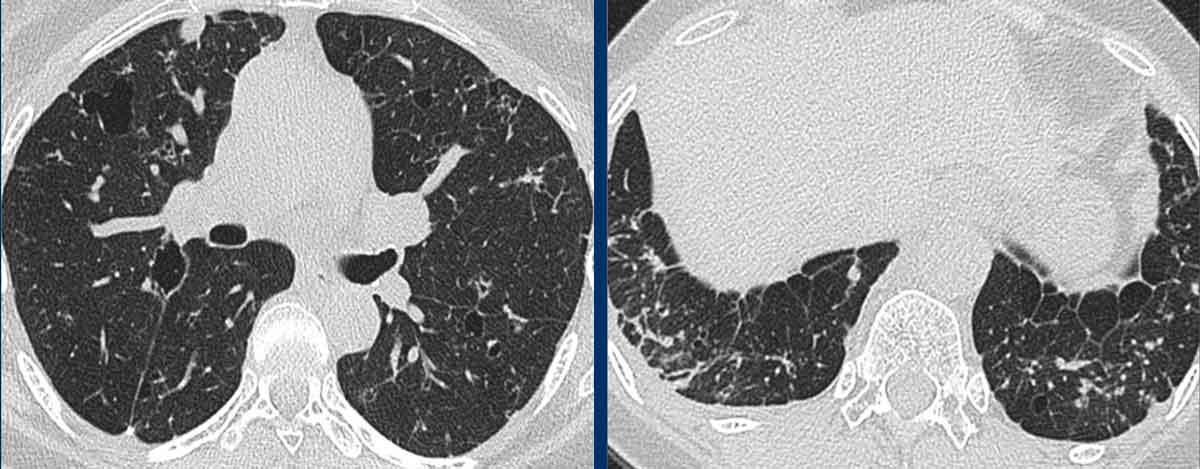

LAM biểu hiện với số lượng lớn các nang hình tròn, bờ đều đặn, phân bố rải rác khắp nhu mô phổi.

- Nhiều nang ở một phụ nữ trẻ. Lưu ý hình dạng tròn đều và phân bố lan tỏa.

- Trường hợp LAM nặng. Khi có tiền sử hút thuốc lá, chẩn đoán phân biệt cần đặt ra là LCH (giai đoạn tiến triển).

- Tràn dịch màng phổi (dịch dưỡng chấp) ở bệnh nhân LAM.

- Phân bố lan tỏa trong LAM.

Các hình ảnh này thuộc về một phụ nữ 39 tuổi với triệu chứng khó thở.

Chẩn đoán có khả năng nhất là gì?

Nhận xét hình ảnh

Có nhiều nang thành mỏng.

Lưu ý các nang phân bố đều khắp hai phổi.

Các ngách màng phổi cũng bị tổn thương (mũi tên).

Điều này cho phép loại trừ chẩn đoán LCH.

Chẩn đoán có khả năng nhất là LAM.